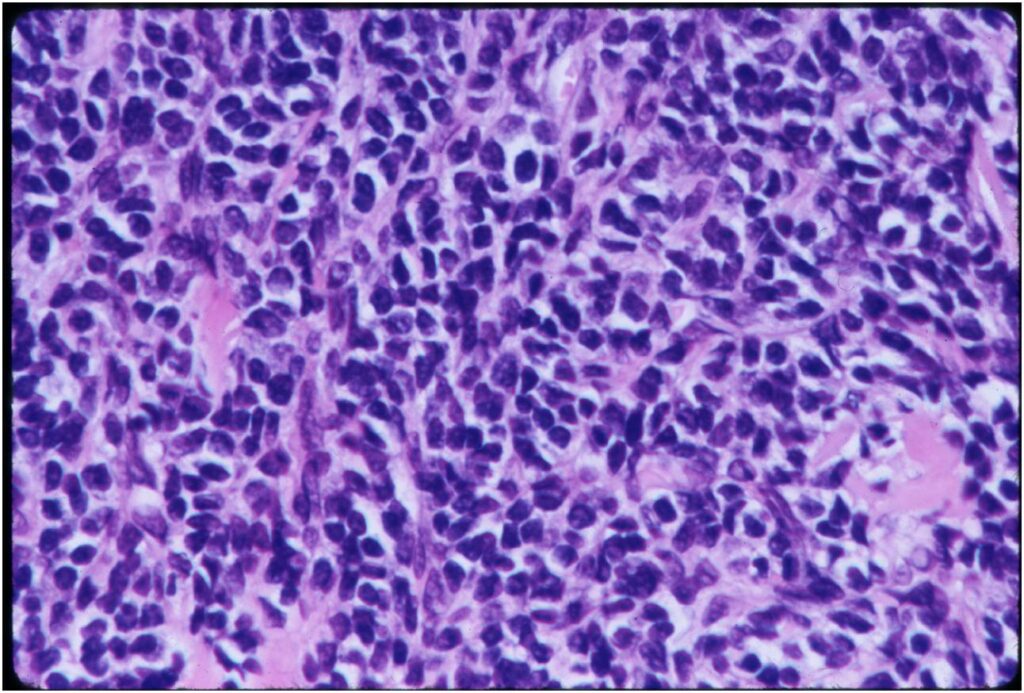

- Neoplastic cells may be small, round, oval, or spindle shaped

- Undifferentiated mesenchymal cells similar to Ewing sarcoma

- Low grade islands of cartilage scattered throughout the mesenchymal cells

- Usually only a small part of lesion

- Cytologically low grade

- Usually sharply demarcated from surrounding stroma